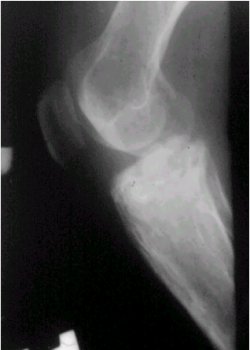

En su presentación clínica, se manifiesta con dolor, es de evolución lenta y su localización es variable. En cuanto a los exámenes radiológicos, en la figura 6 se puede observar una lesión radiolúcida y de ubicación central en la diáfisis tibial.

Figura 6. Radiografía lateral de rodilla que muestra un neurilemoma tibial.